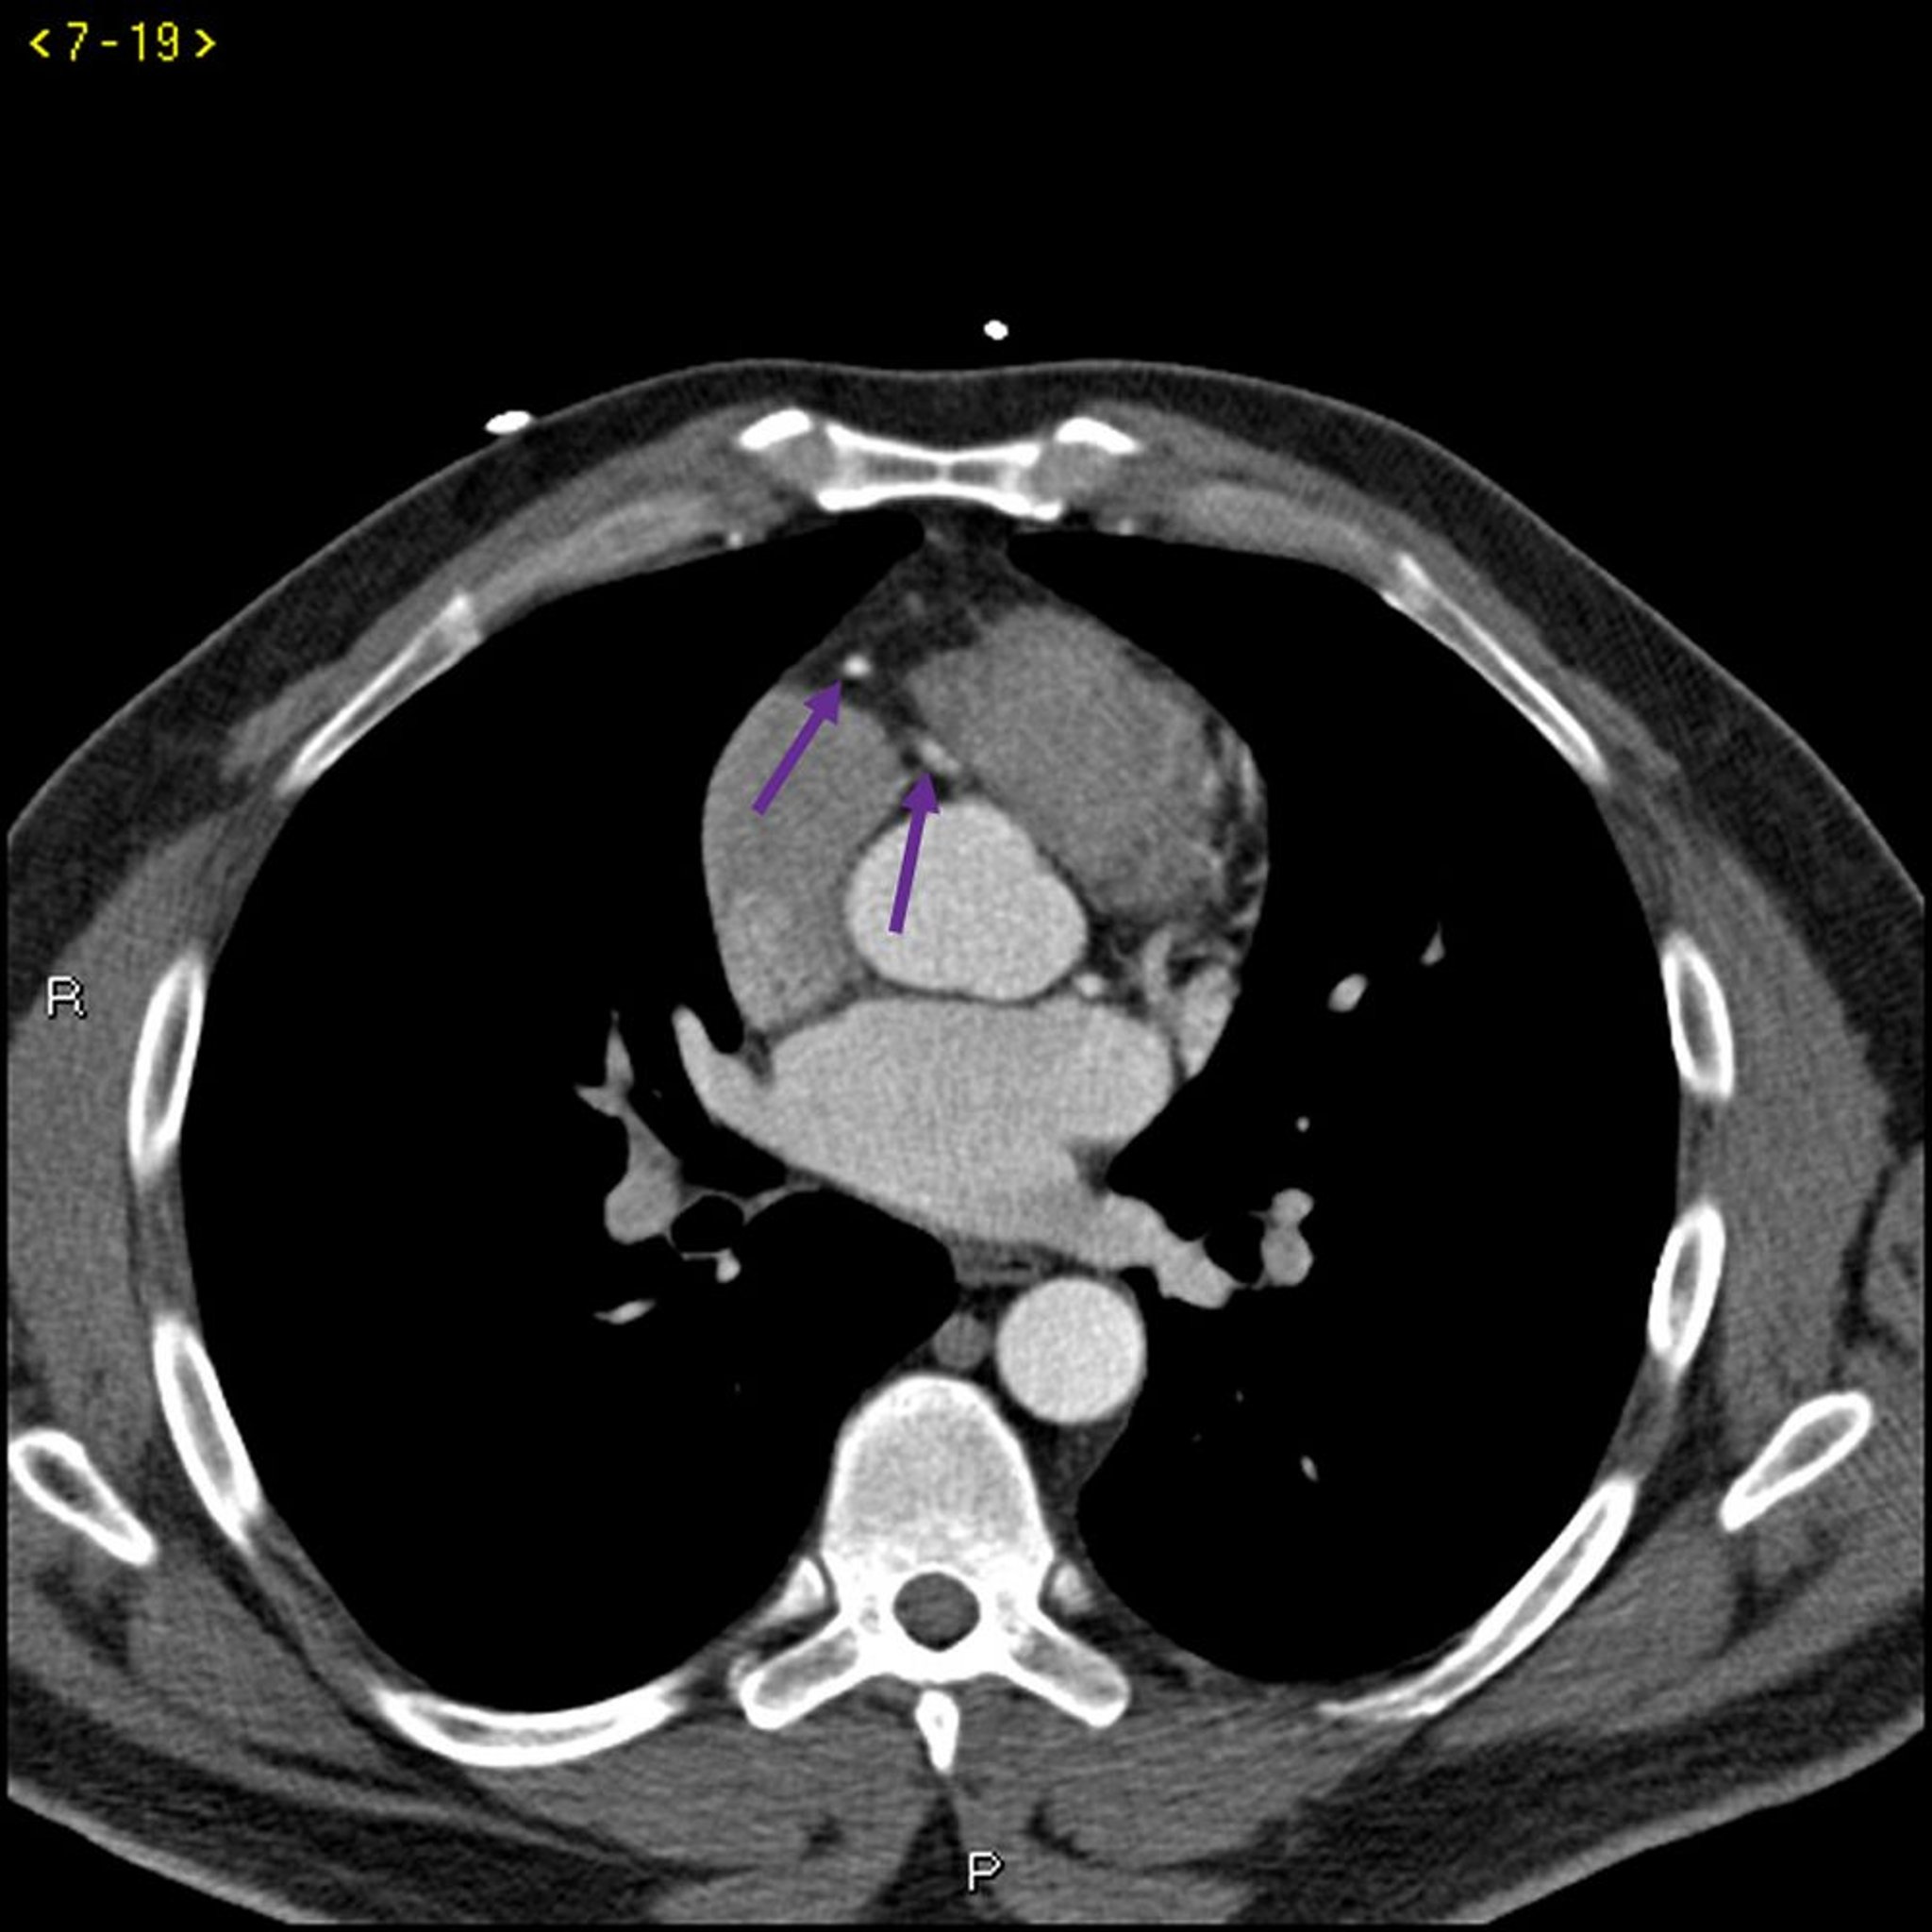

Esta TC con contraste muestra arterias coronarias normales. La arteria principal izquierda está indicada por la flecha roja. Las arterias descendente anterior izquierda y circunfleja izquierda están indicadas por las flechas verde y azul respectivamente, y la arteria coronaria derecha está indicada por la flecha púrpura.